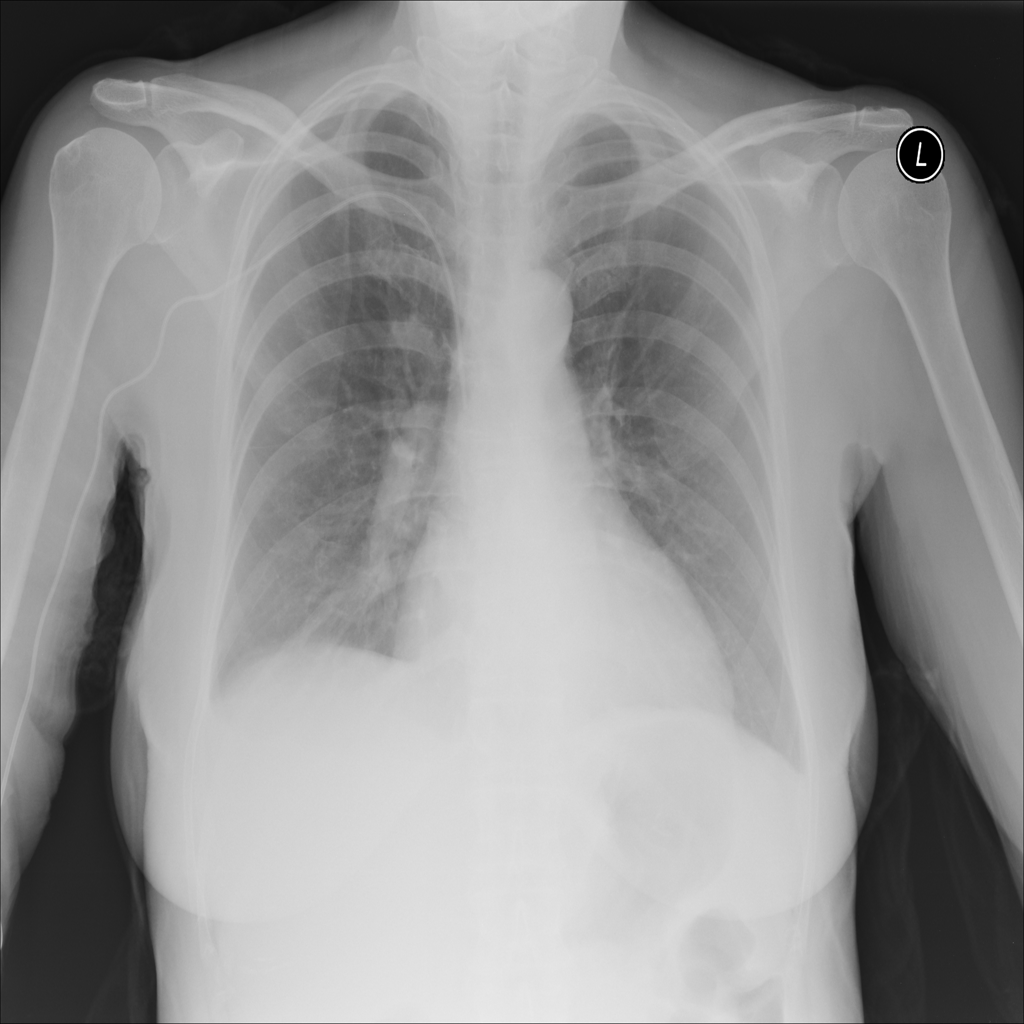

PAT-C0E5 · IMG-007Effusion

PAT-C0E5 · IMG-007

AP